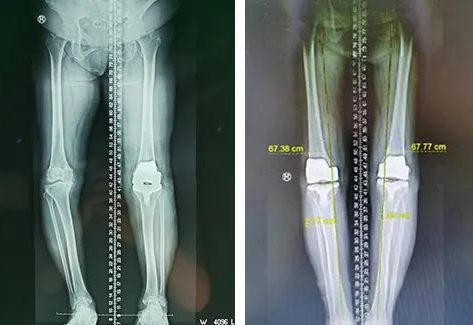

2022年11月,王阿姨左膝关节置换术后片(图左)

2023年2月,右膝关节置换术后片(图右)